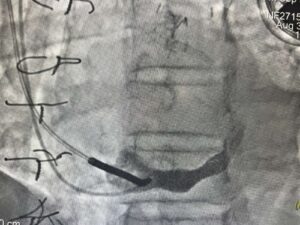

Zabieg wykonywany jest z nakłucia żyły szyjnej i polega na kontrolowanym zwężeniu zatoki wieńcowej przy użyciu rozprężalnego na balonie stentu o kształcie klepsydry. Wskutek zabiegu dochodzi do stopniowego zwężenia pola przepływu przez zatokę wieńcową z redystrybucją przepływu krwi z obszarów o lepszym do obszarów o gorszym ukrwieniu mięśnia sercowego.